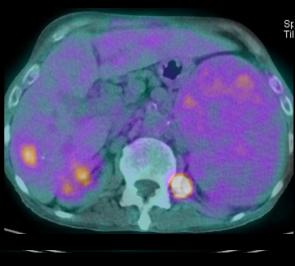

- Bilan d'extention du meme cas en Pet

/CT : Image tres net du tumeure de oesophage 1/3

moyen avec metastase ganglionaire, du foie ,

reins , ganglion pelviene et des os

|